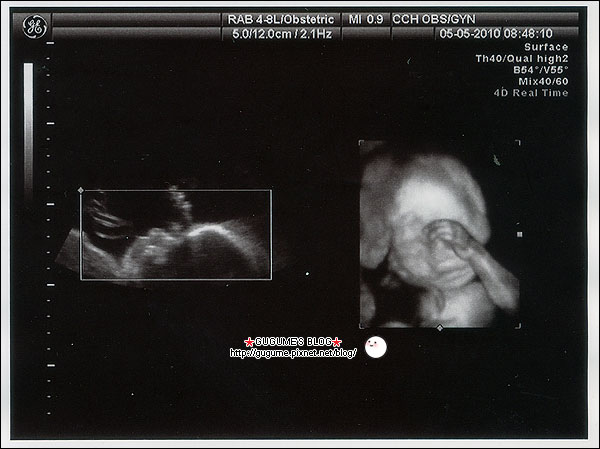

記得產檢時你一直都是很害羞的狀態

常都用小手遮臉不讓阿母看